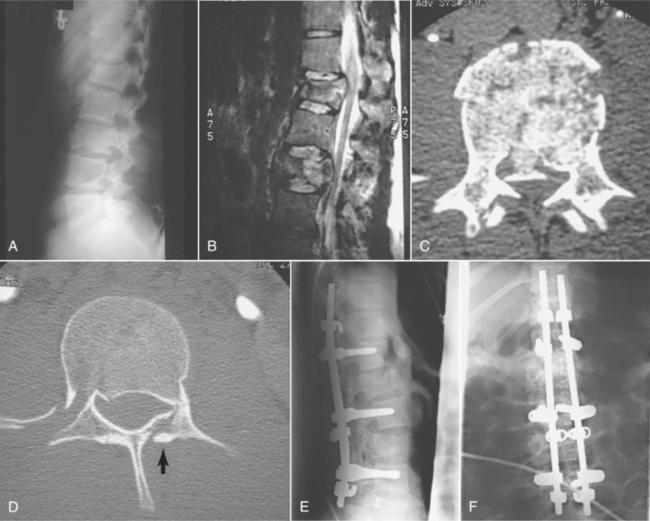

Fig. 34-14 shows a Jefferson fracture seen on x-ray and magnetic resonance imaging (MRI) scan. Fig. 34-15 compares fractures at time of injury and after stabilization. Myelography is indicated for optimal visualization of compression of the spinal cord after trauma. Myelography alone is rarely indicated, and it is used in conjunction with CT. In many cases, MRI has replaced myelography.

Figure 34-15 A 21-year-old man involved in a motor vehicle accident sustained a burst fracture of L1 and L3. The patient had an incomplete spinal cord injury. A, A preoperative lateral view shows loss of height predominately at L1. B, A sagittal-cut magnetic resonance image shows compression at both L1 and L3. C, An axial-cut computed tomographic (CT) scan at L3 shows a retropulsed fragment filling half the canal. D, An axial CT scan at L1 shows a fracture of the lamina and retropulsion of a fragment into canal. E, This injury was stabilized with Isola instrumentation combining both pedicle screws and laminar hooks. Sagittal alignment was maintained. F, Postoperative anteroposterior radiograph showing a cross-connection added for additional stability. (From Browner BD, Jipiter JB, Levine AM, et al: Skeletal trauma: basic science, management, and reconstruction, ed 3, Philadelphia, 2003, Saunders.)